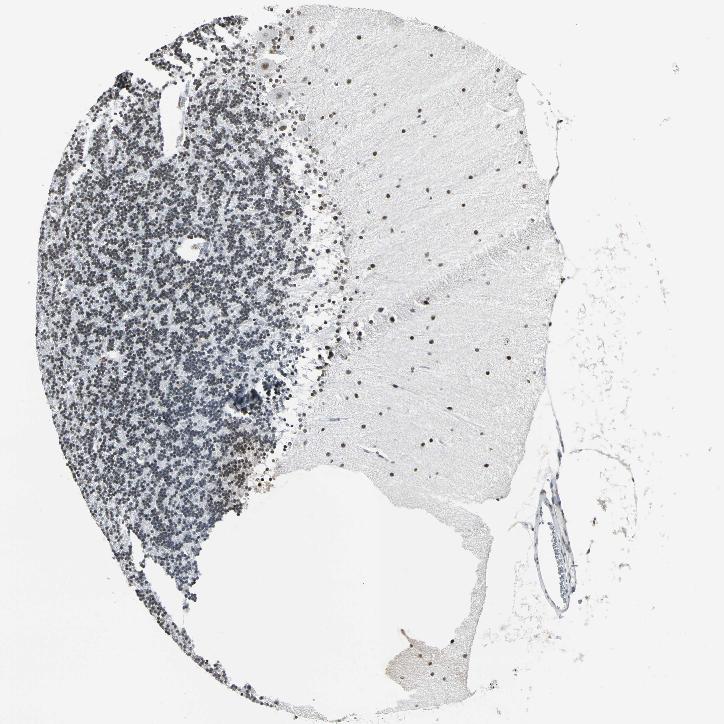

CEREBELLUM - Antibody stainingi

Antibody staining in the annotated cell types in the current human tissue is reported as not detected, low, medium, or high, based on conventional immunohistochemistry profiling in selected tissues. This score is based on the combination of the staining intensity and fraction of stained cells.

Each image is clickable and will lead to virtual microscopy that enables deeper exploration of all samples and also displays staining intensity scores, fraction scores and subcellular localization as well as patient and tissue information for each sample.

Antibody HPA006371

Bergmann glia - cytoplasm/membrane Not detected

Bergmann glia - nucleus High

GLUC cells - cytoplasm/membrane Not detected

GLUC cells - nucleus High

Purkinje cells - cytoplasm/membrane Not detected

Purkinje cells - dendrites Not detected

Purkinje cells - nucleus High

Granular cells - cytoplasm/membrane Not detected

Granular cells - nucleus High

Molecular layer - neuropil Not detected

Molecular layer cells - cytoplasm/membrane Not detected

Molecular layer cells - nucleus High

Processes in granular layer Not detected

Processes in molecular layer Not detected

Processes in white matter Not detected

Synaptic glomeruli - capsule Not detected

Synaptic glomeruli - core Not detected

White matter cells - cytoplasm/membrane Not detected

White matter cells - nucleus High